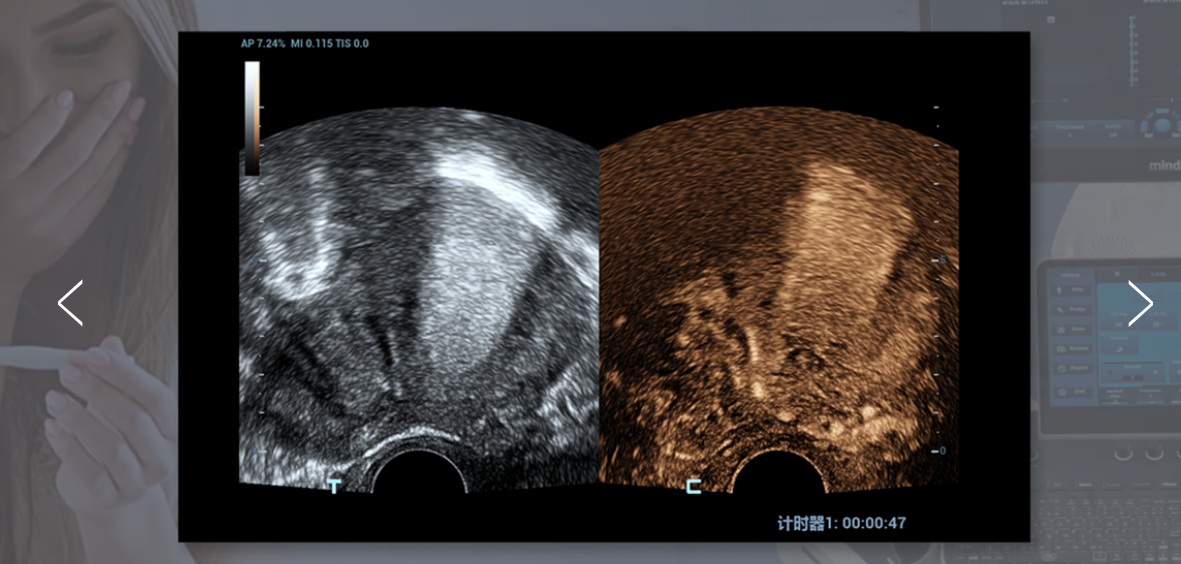

UWN+ (Ultra-Wideband Non-linear Plus) CEUS տեխնոլոգիան Nuewa R9-ին հնարավորություն է տալիս հայտնաբերել և օգտագործել թե՛ երկրորդ հարմոնիկան, թե՛ ոչ գծային հիմքային ազդանշանները՝ ստեղծելով զգալիորեն բարելավված պատկերներ, ինչը բարձրացնում է զգայունությունը և երկարացնում տեսագրության/դիտարկման տևողությունը՝ գինեկոլոգիական հիվանդությունները ավելի լավ հասկանալու համար։